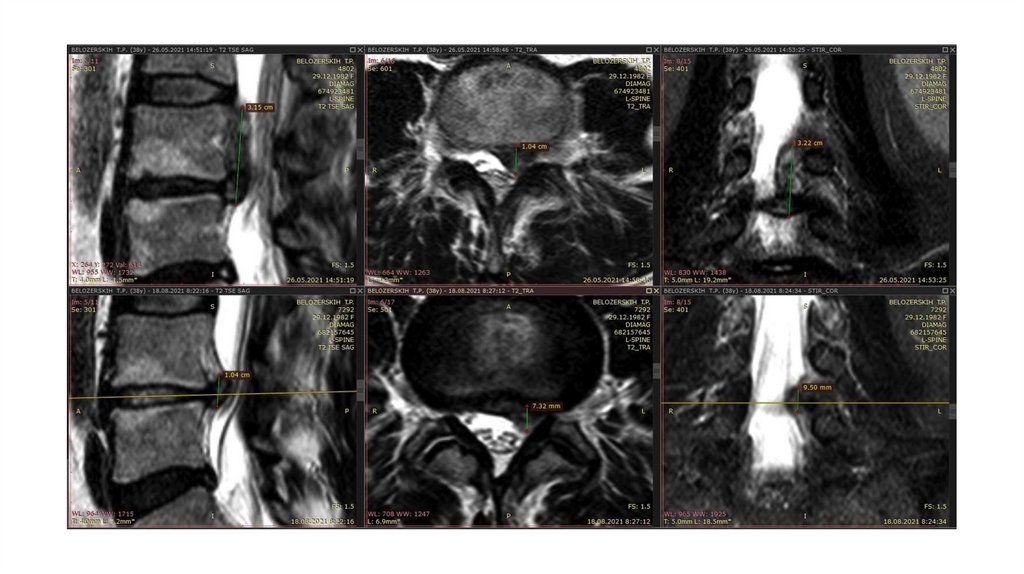

Спонтанный регресс грыжи

У некоторых пациентов может

наблюдаться уменьшение размеров грыжи

по результатам визуализационных

исследований . Данный феномен носит

название спонтанной резорбции

(регрессии) грыжи, которая может быть

как частичной, так и полной.

Однако частота регресса, условия его

развития, возможные механизмы и

влияние

на клиническую симптоматику остаются

не совсем ясными.

Ученые сделали вывод, что больные с

секвестрированными грыжами имеют

лучшие шансы на успешное

консервативное лечение, что,

вероятно, связано с воспалительной

19.